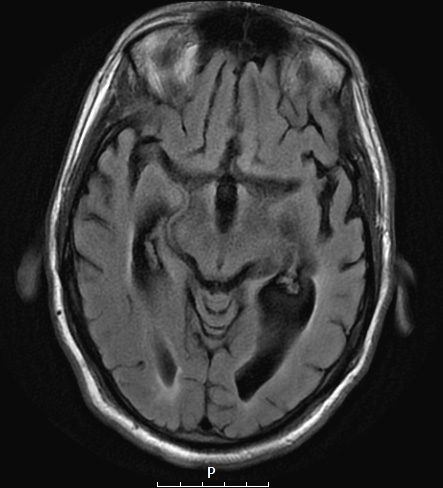

Washington University Experience | NEURODEGENERATION | Pick Disease | 11A2 Pick Dz (Case 11) T2FLAIR 2 - Copy - Copy

These axial FLAIR images demonstrate marked ventricular dilatation and substantial frontal, temporal (and parietal) lobe atrophy